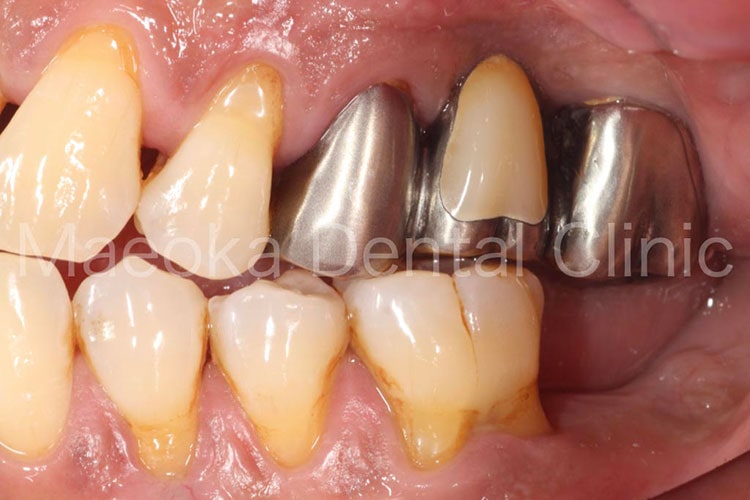

患者さんは54歳の男性の方で、「左下の入れ歯が噛むたびに痛くて違和感があるので診て欲しい。」という主訴で来院されました。

お口の中を拝見すると左下に義歯が装着されている状態で、上顎に偏った欠損が存在していることで左上の歯が噛む度に義歯を歯肉に押し込み、痛みを惹起していました。

患者さんと相談し、先ずは全顎的な歯周病の治療を行って歯肉を健全な状態に戻した上でインプラント治療によって固定式の治療を行うこととしました。

左下には4歯分の欠損があったため4本のインプラントを埋入することも検討しましたが、残っている骨の状態(厚みや高さ)を考慮し、最小限の2本だけ埋入し、被せ物を延長する形で対応しました。

結果として、インプラント治療のコストを抑えつつも清掃性を確保した欠損補綴を行うことができました。

治療の初期に患者さんのプラークコントロールが向上したことで、インプラントの箇所も日々綺麗な状態で管理されています。

治療前(正面)

治療後(正面)

治療前(下顎咬合面)

治療後(下顎咬合面)